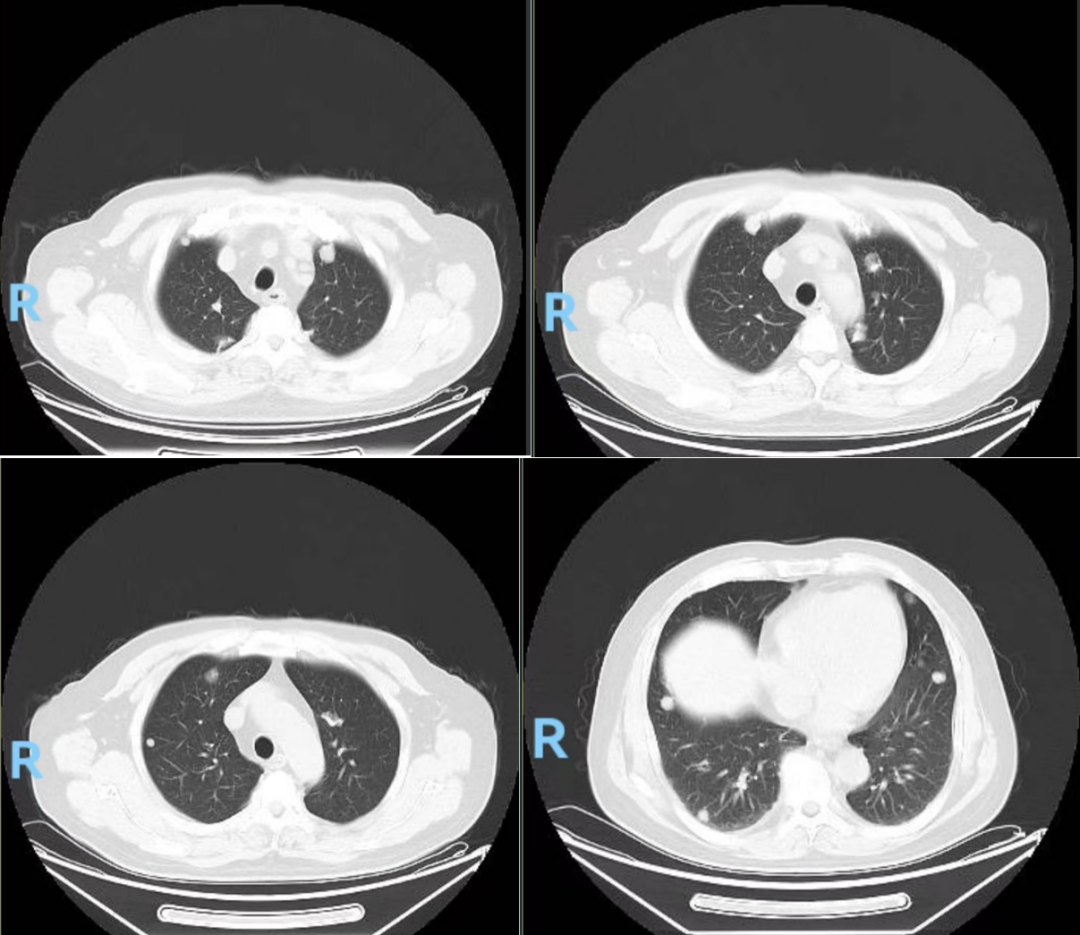

胸部CT(图2,2024-04-18):1.双肺多发结节灶、纵隔、腹膜后多发淋巴结肿大,考虑:肺内多发转移,纵隔淋巴结转移、腹膜后淋巴结转移可能;2.T9椎体骨质破坏,转移可能大。

图2.胸部CT(2024-04-18):双肺可见多发结节状密度灶,较大者直径约2cm,右肺中叶外侧段支气管受压,欠通畅。纵隔3、4R、6、7、10R区可见多发肿大淋巴结。T9椎体可见骨质破坏,密度欠均。诊断:1.双肺多发结节灶、纵隔、腹膜后多发淋巴结肿大,考虑:肺内多发转移,纵隔淋巴结转移、腹膜后淋巴结转移可能;2.T9椎体骨质破坏,转移可能大